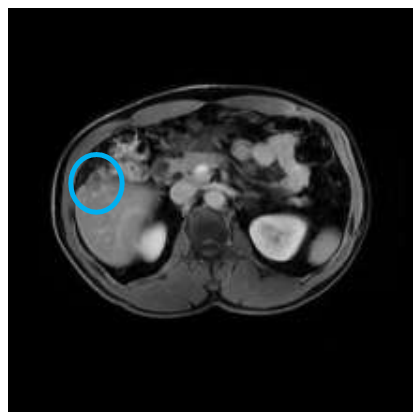

+ Khám định kỳ theo hẹn bệnh ổn định, không thấy tổn thương tái phát di căn, tổn thương gan giảm kích thước và không ngấm thuốc đối quang từ.

Hình 3. Hình ảnh khối gan phải hạ phân thùy V kích thước 19×14 mm, không ngấm thuốc sau tiêm (vòng tròn xanh).